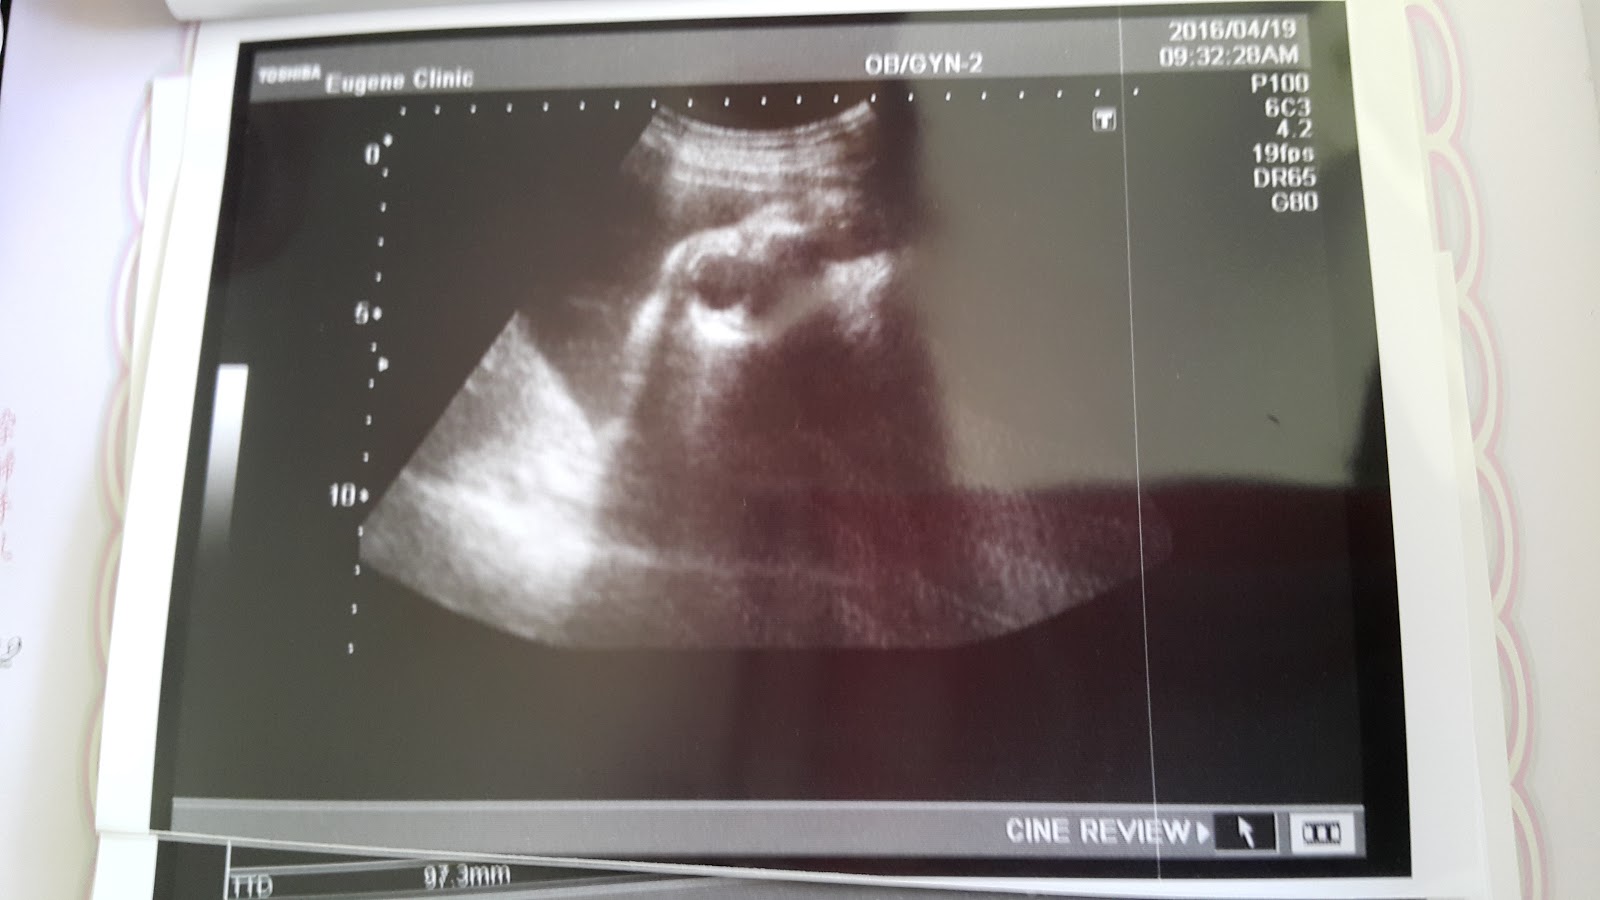

Haru 小妞,這是你的臉嗎?

是嘴巴開開嗎?正在睡覺嗎?

還是??

看平面照片很像嘴巴張開,在電腦上看很像你的嘴巴側面照,這樣